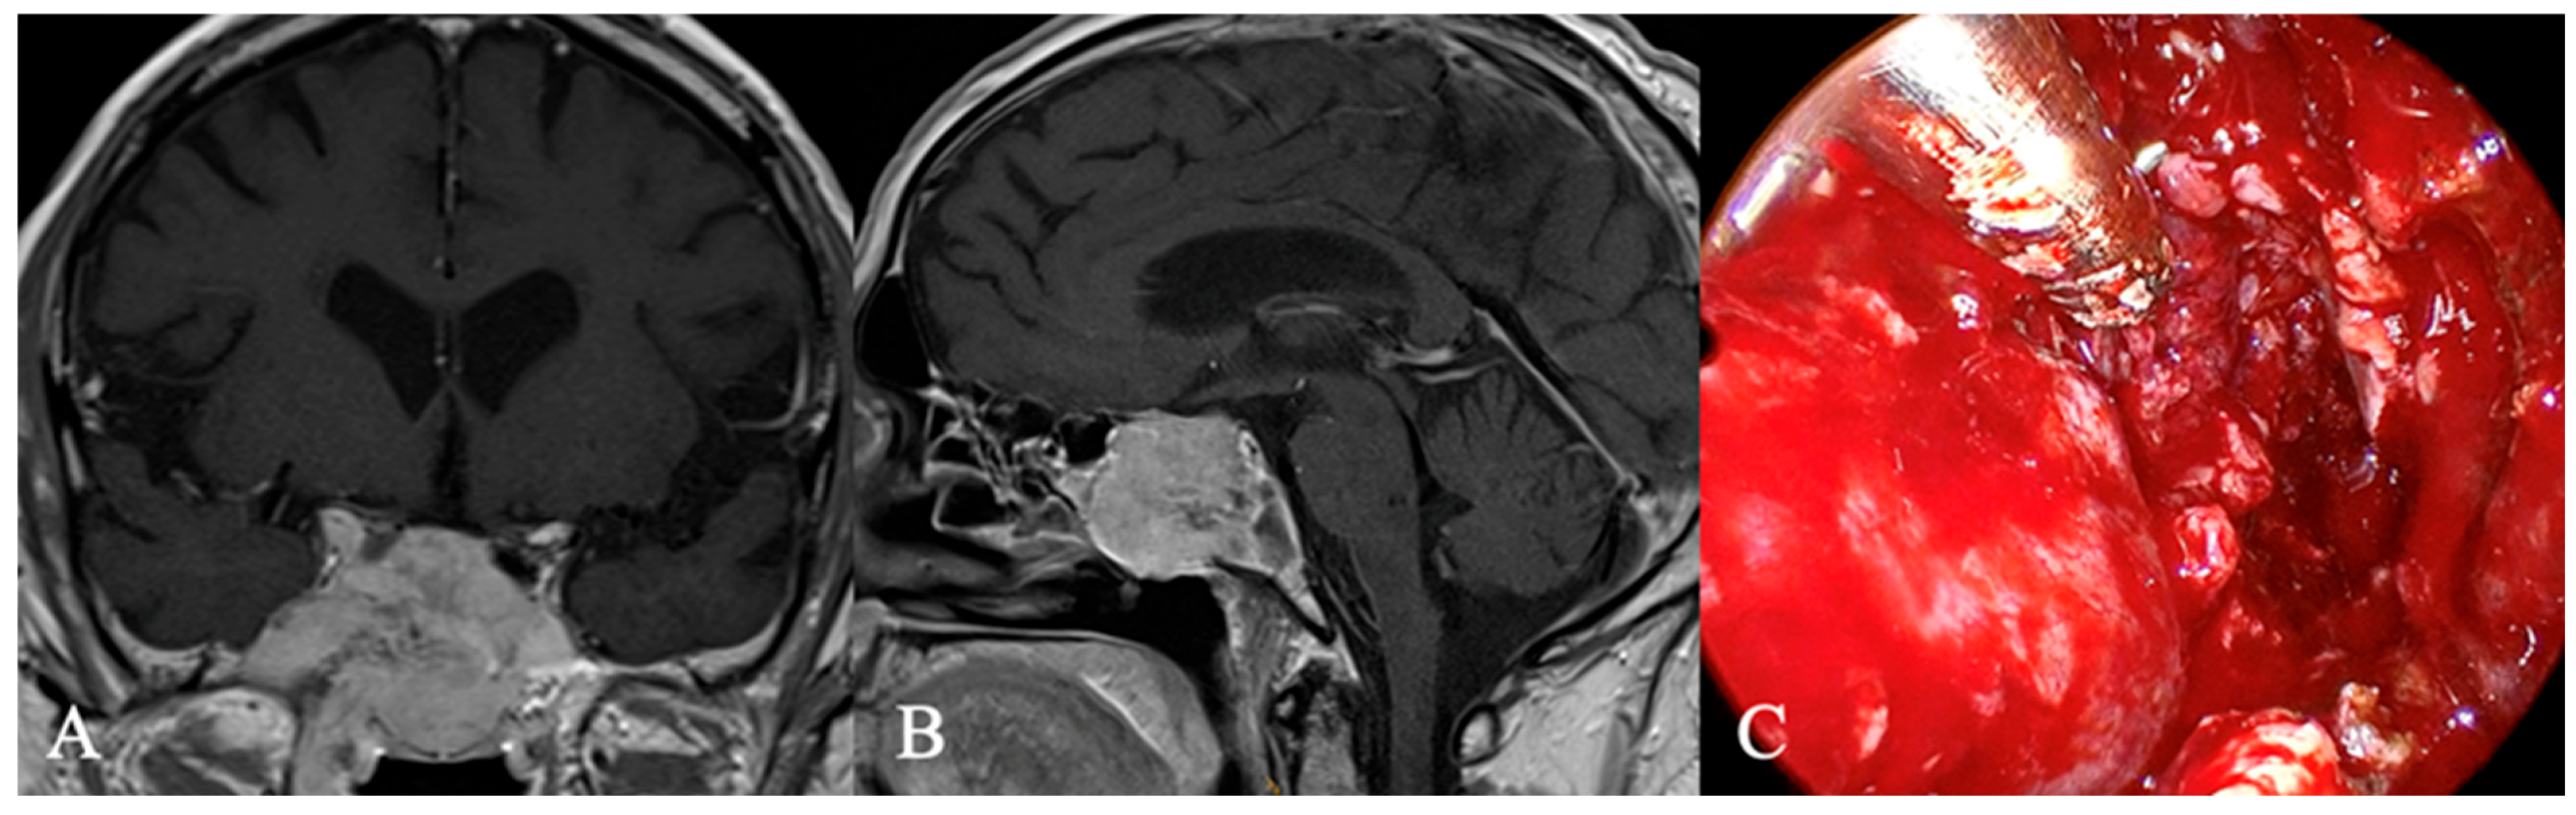

4.2. Differential Diagnoses and Case Presentations